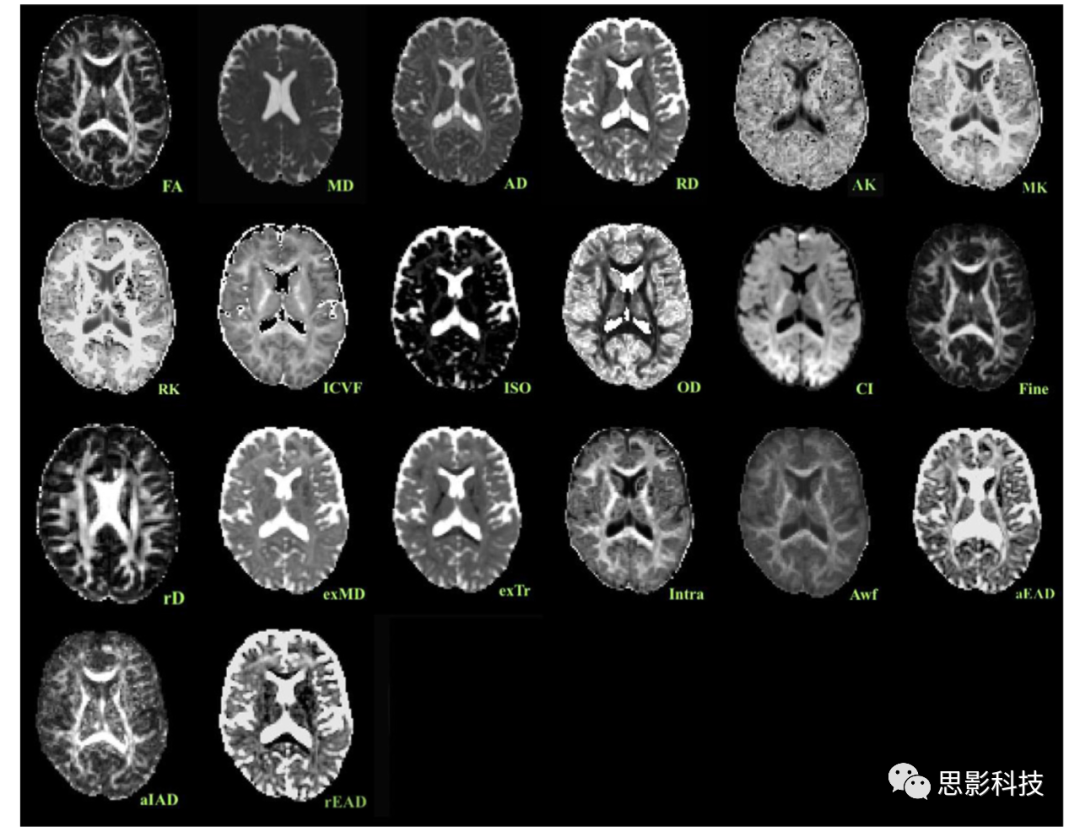

基于最近的研究,本文從六個模型(DTI、DKI、NODDI、RSI、SMT mc、WMTI)中選擇了20個標量指標。我們還根據(jù)與我們的采集協(xié)議相關(guān)的可行性和開源腳本的可用性來選擇模型。出于說明性目的,2顯示了一個參與者的所有用到的指標。使用從一系列感興趣區(qū)域提取的所有可用指標進行腦齡預測。

2:來自一個參與者的擴散指標。

DTI:FA(各向異性分數(shù))、MD(平均擴散系數(shù))、AD(軸向擴散系數(shù))、RD(徑向擴散系數(shù))。

DKI:AK(軸向峰度)、MK(平均峰度)、RK(徑向峰度)。

NODDI:ICVF(細胞內(nèi)體積分數(shù))、ISOVF(各向同性體積分數(shù))、OD(方向分散度)。

RSI:CI(細胞指數(shù))、Fine(FA fine scale/slow compartment)、rD(限制擴散系數(shù))。

SMT mc:exMD(細胞外間隙)、exTr(橫向細胞外間隙)、Intra(軸突內(nèi)擴散率)。

WMTI:Awf(軸突含水率)、aEAD、aIAD(軸向內(nèi)外彌散系數(shù))、rEAD(軸向軸突外彌散系數(shù))。